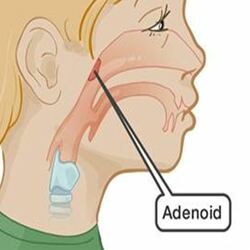

Adenoidectomy

Adenoidectomy Surgery in Bangalore

Adenoidectomy is a surgical process to remove an adenoid for reasons that include impaired breathing through the nose, chronic infections, or recurrent earaches. The effectiveness of removing the adenoids in children to improve recurrent nasal symptoms and/or nasal obstruction. The surgery is less commonly performed in adults in whom the adenoid is much smaller and less active than it is in children it is most often done under general anesthesia. Post-operative pain is generally minimal and reduced by icy or cold foods. Dr.Yashaswi has been performing adenoidectomy surgery in Bangalore for around 14 years.